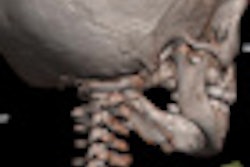

Virtual autopsies can play a role in cases of suspected child abuse. In this image, volume-rendered cranial postmortem CT data suggested an atlanto-axial rotatory subluxation. Note the position of the right lateral mass of the first cervical vertebra compared with the column of right lateral masses of the lower vertebras. This is a nonaccidental finding in many postmortem CT examinations. All images courtesy of Dr. Anders Persson, PhD, Center for Medical Image Science and Visualization, Linköpings Universitet, Sweden.Despite this high interest, administrative, legal, and financial obstacles have delayed adoption in France. The government recognizes a virtual autopsy as a medical act and has defined pivotal centers that are reimbursed for the exam, yet the question of who is paid for what services remains open because the reimbursement is received by the hospital and not the practicing radiologist, noted Dr. Bernard Proust, from the Centre Hospitalier Universitaire de Rouen (CHU-Rouen) in France.